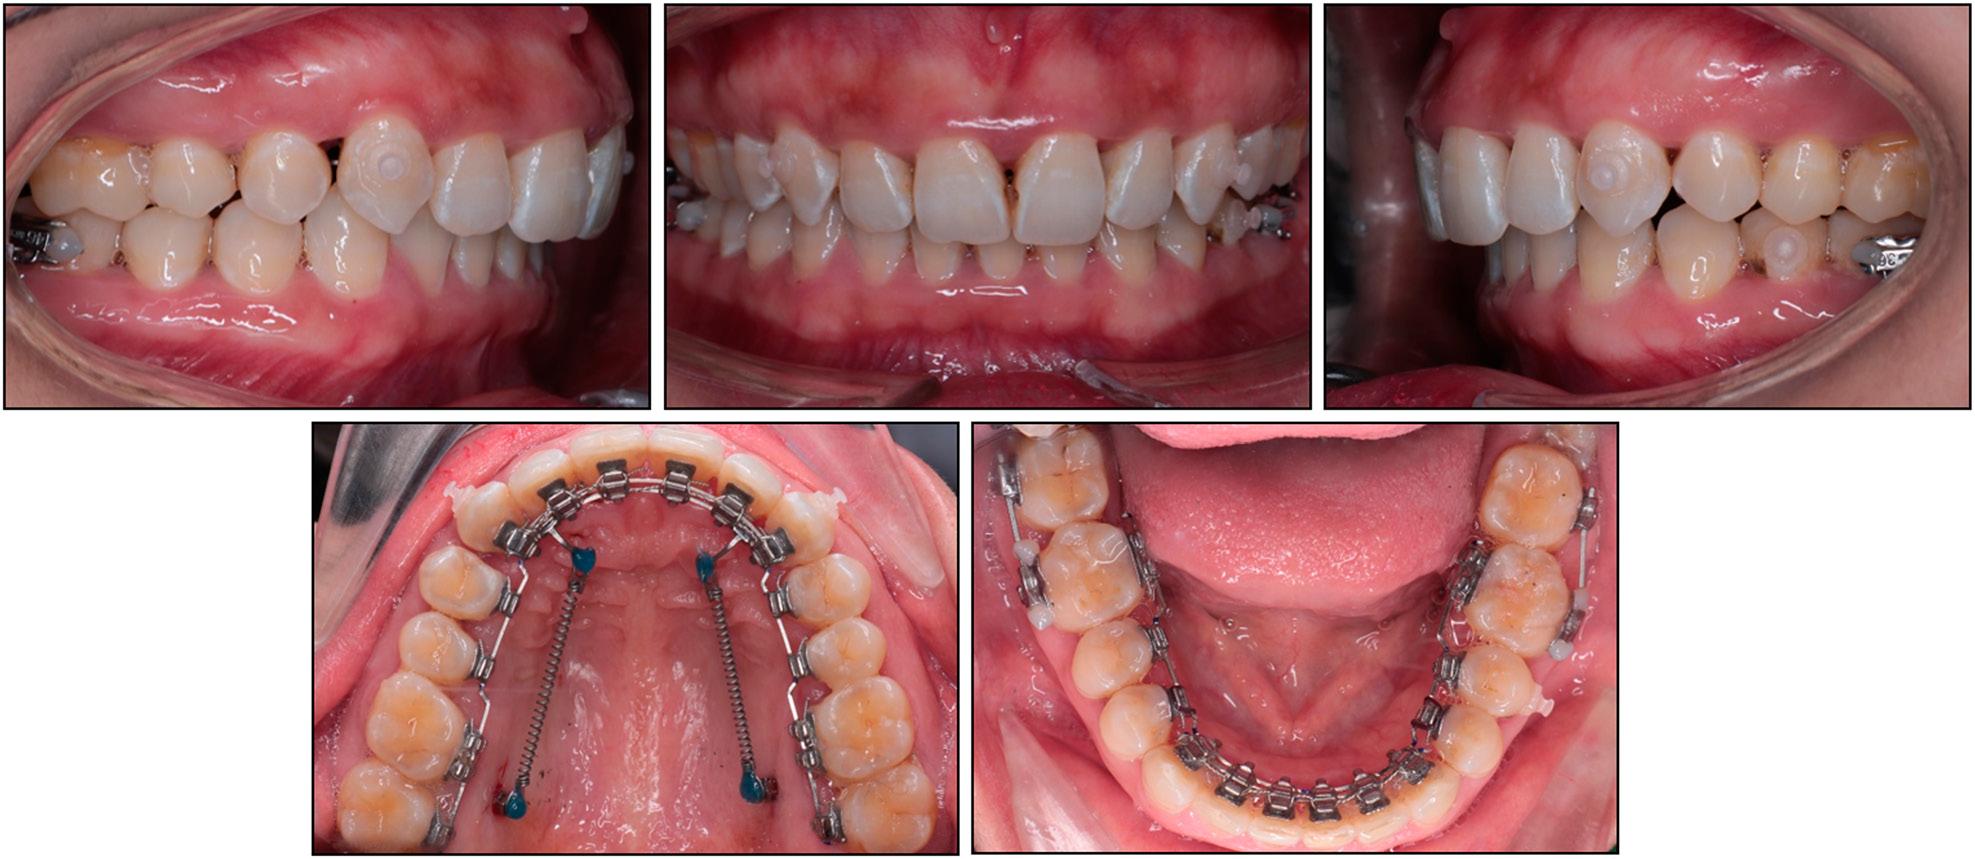

After 21 months of treatment, a dental Class I relationship with a normal overbite and overjet was achieved (Figure 4). During the finishing stage, some labial brackets were bonded to improve tooth alignment (cross-over technique).2 Interproximal stripping was performed on the upper and lower incisors to reduce the gingival black triangles. The total treatment time was 27 months. After lingual appliance removal, fixed retainers were placed in both arches along with Essix retainers for nighttime wear.

Finishing and detailing stage. Gingival black triangles before interproximal stripping.

Post-treatment records show satisfactory results with a well-aligned dentition and improved smile aesthetics (Figure 5). Solid Class I canine and molar relationships were obtained on both sides along with a normal overbite and overjet. The upper anterior torque was improved and the curve of Spee was levelled. The excessive gingival exposure when smiling was eliminated. The two-year post-retention records showed the stability of the treatment results without signs of relapse (Figure 6).

Case 1: post-treatment extraoral and intraoral photographs.